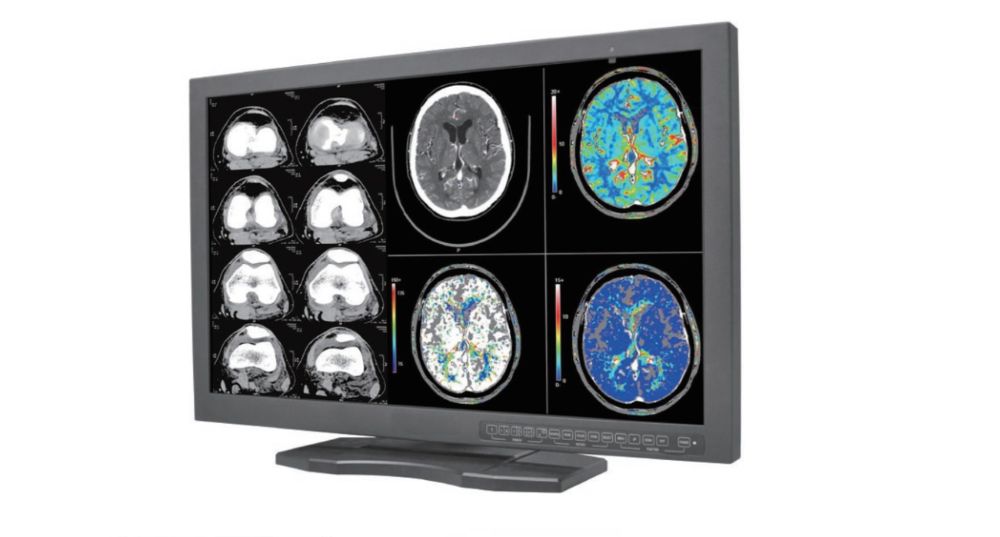

Innowave Healthcare Powering Next-Gen Imaging Workflows Through Innovation

Advanced Imaging, Diagnostics, and AI Solutions for Enhanced Patient Care and Streamlined Workflows

Featured Products

Cutting-Edge Products

Innowave Healthcare is a leading Indian MedTech software company revolutionizing diagnostic imaging since 2013. We offer AI-powered PACS-RIS, teleradiology, tele-ophthalmology, and workflow solutions trusted by diagnostic centers and hospitals across India, Southeast Asia, West Asia, Africa, and North America. Our flagship Freedom Nano platform is a cost-effective, multi-specialty workflow system supporting radiology, cardiology, ophthalmology, and more. We empower clinicians with fast, accurate, and connected diagnostics—even in remote locations. At Innowave, we innovate to make healthcare smarter, more accessible, and truly transformative.